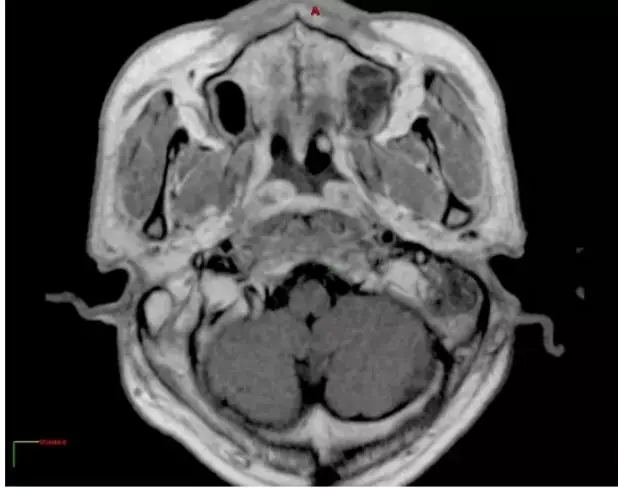

治疗7个月后MR图像,肿瘤缩小70%